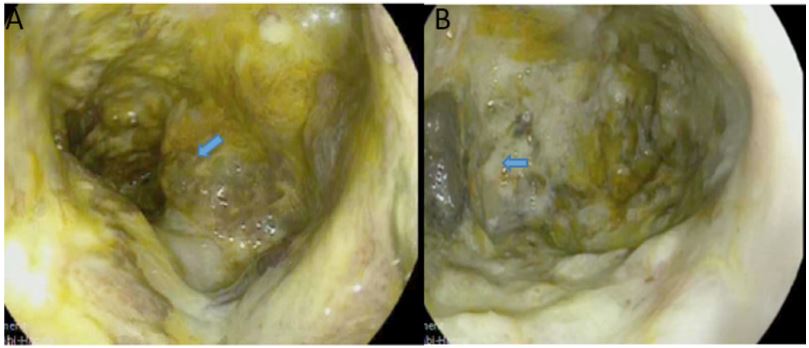

A 70-year old female was referred to the emergency department of a tertiary hospital by her general practitioner with a sixmonth history of lethargy, six-kilogram weight loss and vague right sided abdominal pain. She denied vomiting, altered bowel habit or rectal bleeding. Her relevant surgical history included cholecystectomy and thyroidectomy. There was no family history of colorectal cancer. Pertinent examination findings included a soft, non-distended abdomen with a large non-mobile palpable mass in the right upper quadrant. Her blood profile included leukocytosis (12.9 x109 /L), anaemia (Hb 79 g/L), normal bilirubin and mildly deranged liver function tests. Furthermore, she had a markedly raised CA 19.9 (5506 kU/L) and CEA (462.1 microg/L). She was admitted for a blood transfusion and further investigations. A triple phase computed tomography scan of the chest, abdomen and pelvis revealed an 11x10x10.5 cm hepatic flexure mass with invasion into the right hepatic lobe (Figure 1). Surprisingly, there was no evidence of colonic obstruction, nor distant metastatic disease. A colonoscopy demonstrated a large circumferential, fungating and partially obstructing mass extending into the ascending colon (Figure 2). Biopsy confirmed a poorly differentiated invasive adenocarcinoma (Figure 3). Following discussion at a multi-disciplinary surgical oncology meeting, she proceeded to an ileo-colonic bypass with planned adjuvant chemotherapy. Intra-operatively, the mass was invading the liver, with small amounts of ascites and no peritoneal metastasis. Proximal small and large bowel were of normal caliber. An ileo-colic side-to-side anastomosis was performed using the distal ileum and mid transverse colon. The patient made an uneventful recovery and was discharged day four post operatively with medical oncology follow up.

Figure 1: Axial (A) and coronal (B) computed tomography images of the hepatic flexure neoplasm (Blue arrow) invading the right liver lobe.